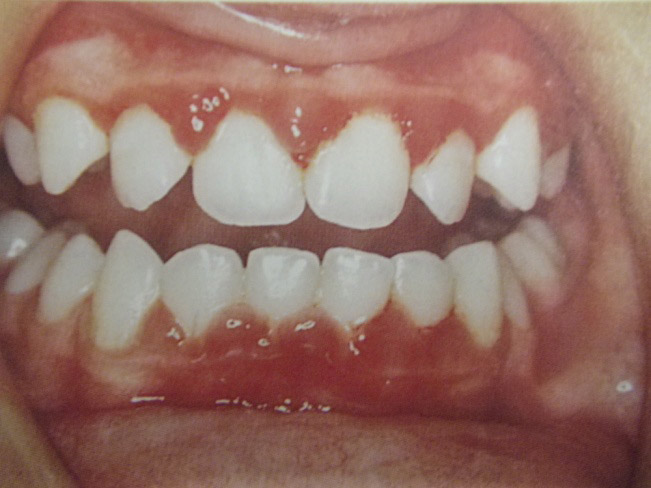

Ουλίτιδα

Η νόσος της ουλίτιδας:

- Εκδηλώνεται με διόγκωση και ερυθρότητα των ούλων γύρω από τα δόντια.

- Το κυριότερο χαρακτηριστικό είναι η αιμορραγία των ούλων στο βούρτσισμα και ορισμένες φορές συνοδεύεται από πόνο και κακοσμία του στόματος.

- Οφείλεται, όπως και η τερηδόνα, στη μικροβιακή πλάκα δηλαδή στα μικρόβια που προσκολλώνται στα δόντια και τα οποία έρχονται σε επαφή με τα ούλα προκαλώντας τοπικά φλεγμονή.

- Μπορεί εύκολα να προληφθεί με σωστό και καθημερινό βούρτσισμα των δοντιών, τη χρήση οδοντικού νήματος και των στοματικών διαλυμάτων σύμφωνα με της οδηγίες του παιδοδοντίατρου. Σημαντικός είναι επίσης ο τακτικός έλεγχος των δοντιών στον παιδοδοντίατρο και ο καθαρισμός των δοντιών 1-2 φορές το χρόνο.